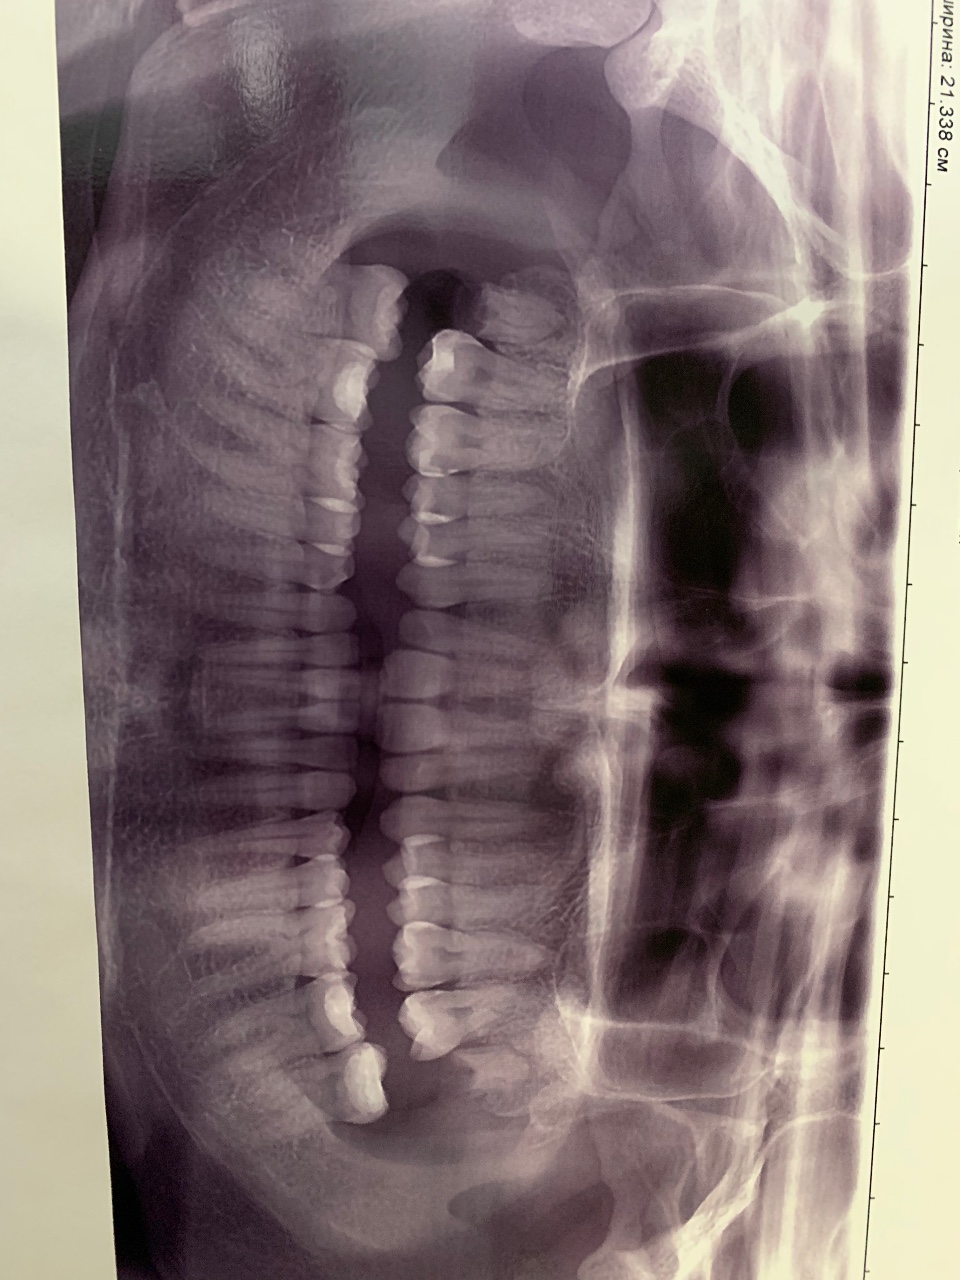

Рентгенография небного шва: Медицинские исследования и диагностика